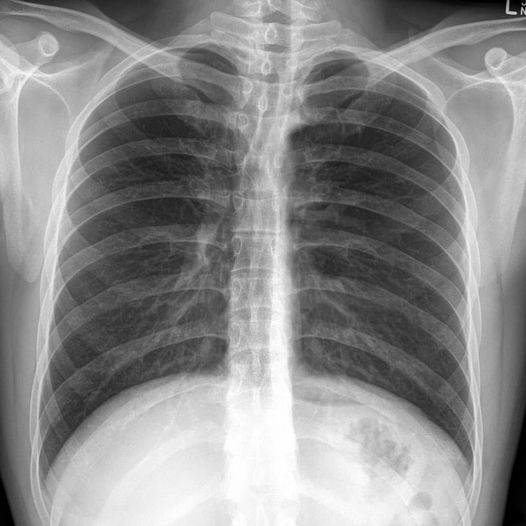

Donald Trump’s chest roentgenogram has been released.

Someone thought it wasn't his because it shows a backbone.